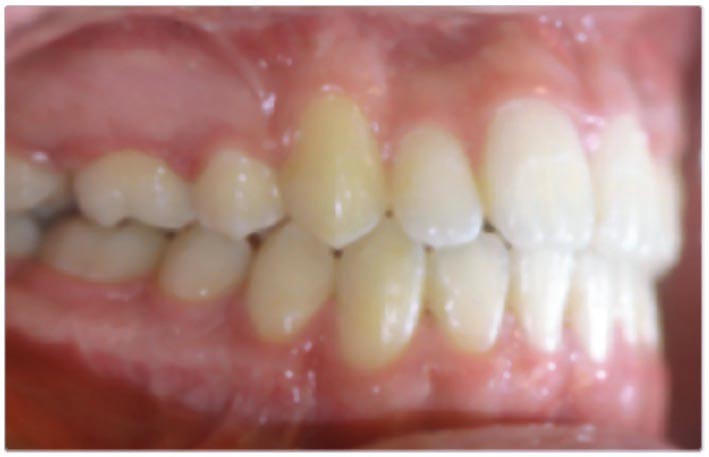

Bastien présente à l’âge de 8 ans les mêmes symptômes de dolichomandibulie…